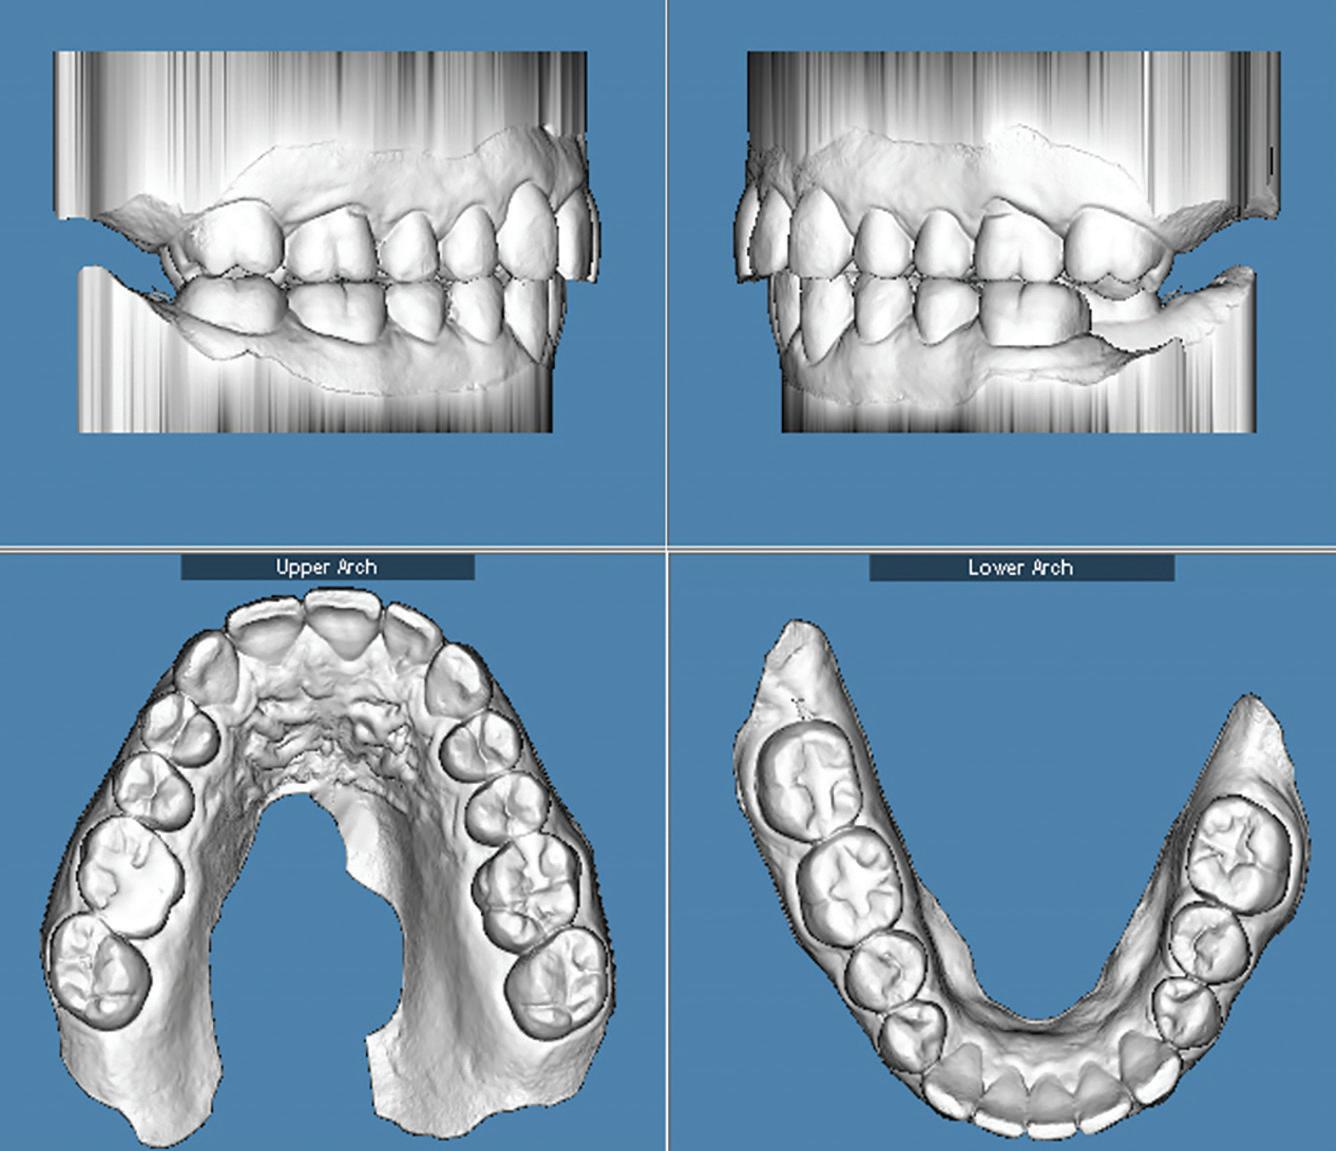

Clear aligner therapy and symptoms of temporomandibular disorders: a case report

Lina Sharab

Bushra Butul

Aqib Shafi

Jeffrey P. Okeson

SELF-INSTRUCTION EXERCISE GD538, 2 CE CREDITS, P. 53